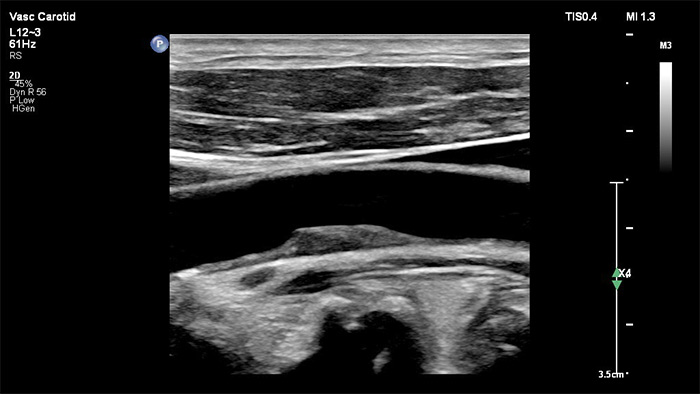

La sonde xMATRIX XL14-3 intègre 56 000 éléments remarquables, chacun connecté à un microcanal séparé. La sonde XL14-3 offre une focalisation électronique multidimensionnelle pour une imagerie échographique en coupes ultrafines de l’anatomie vasculaire et de la morphologie de plaque. Atout majeur : une fiabilité du diagnostic exceptionnelle lors de l’évaluation d’une sténose et d’une plaque vulnérable.

La sonde xMATRIX XL14-3 offre une imagerie xPlan qui va au-delà de l’approche conventionnelle des examens vasculaires, en fournissant des images en temps réel, simultanément dans des plans longitudinaux et transversaux. Atout majeur : avec l’imagerie xPlan, il n’est plus nécessaire de faire pivoter la sonde pour obtenir des vues orthogonales. Un simple mouvement de la boule de commande permet d’obtenir une évaluation anatomique complète, ce qui permet de gagner du temps lors de l’examen.

Le traitement nouvelle génération des images de Philips améliore l’imagerie vasculaire en offrant une superbe délimitation des interfaces vasculaires et une meilleure perception de la texture de plaque. En réduisant le flou dans les vaisseaux et les artefacts, XRES Pro améliore la fiabilité du diagnostic lors de la réalisation d’examens d’imagerie vasculaire chez les patients, y compris ceux qui sont techniquement difficiles.